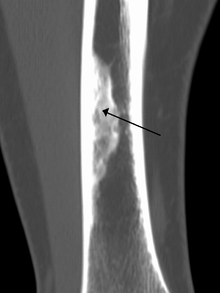

A nonossifying fibroma (also called fibroxanthoma) is a fibrous bone lesion that is usually asymptomatic and discovered as an incidental finding on x-ray. It is the most common benign bone tumor in children and adolescents. However, it is controversial whether it represents a true neoplasm or rather a developmental disorder of growing bone. Radiographically, the tumor presents as a well marginated radiolucent lesion, with a distinct multilocular appearance. These foci consist of collagen rich connective tissue, fibroblasts, histiocytes and osteoclasts. They originate from the growth plate, and are located in adjacent parts of the metaphysis and diaphysis of long bones, most often of the legs. No treatment is needed in asymptomatic patients and spontaneous remission with replacement by bone tissue is to be expected.